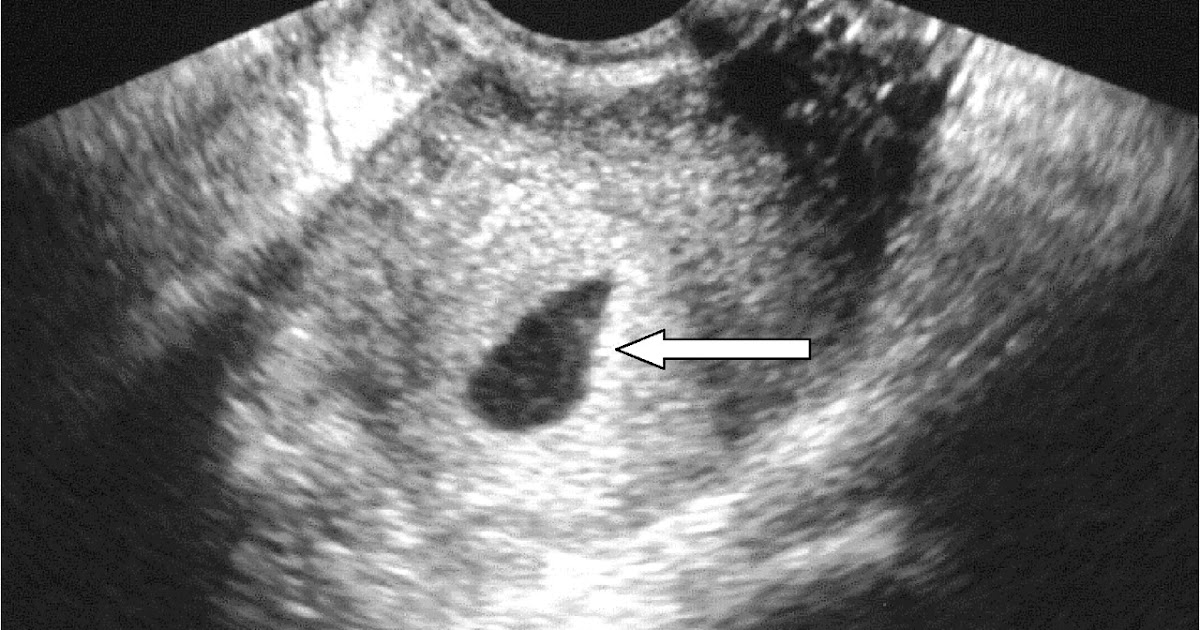

Detección de Anomalías en la Formación Neurológica

El ultrasonido obstétrico se ha convertido en una herramienta esencial para la detección de posibles anomalías en la formación neurológica fetal. Durante el proceso de exploración, los médicos pueden identificar signos de hidrocefalia, espina bífida y otras condiciones que afectan el sistema nervioso central del feto. La prontitud en la identificación de estas anomalías es crucial para tomar decisiones informadas sobre la atención médica necesaria.